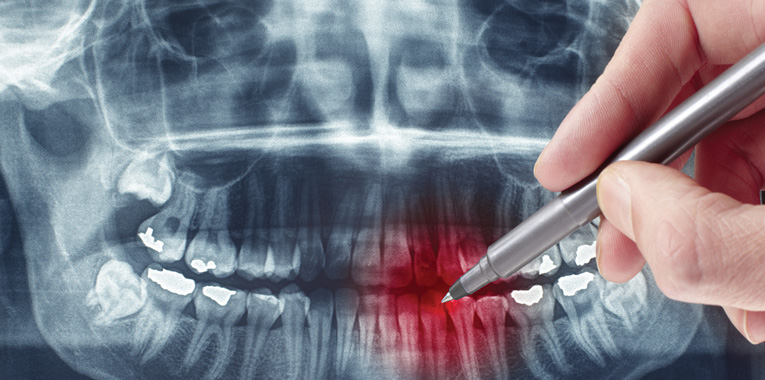

Sorrir abre portas: no mercado de trabalho e nos relacionamentos, é o sinal mais característico da felicidade. Nada mais justo que cuidar muito bem de nossa boca e de nossos dentes para poder expressar a alegria, simpatia e a sinceridade da melhor forma. O cirurgião-dentista Dr. Antonio Hercules Filho, do Centro Odontológico Londrinense, define que tratar bem da boca vai muito além da parte estética. “É preciso cuidar dos materiais que serão utilizados e planejar com cuidado o tratamento, que é individualizado para atender à necessidade de cada pessoa”.

Ele começa dando o exemplo de um tratamento muito procurado atualmente, o uso de próteses para preencher a ausência de dentes. “Uma prótese começa com a perfeição do preparo que o profissional deve fazer no local. Faz-se a prótese provisória primeiro, que, muitas vezes, de tão bem feita não precisa nem ser colada, pois se adapta perfeitamente à boca. Depois fazemos a prótese definitiva, com o tamanho e forma ideal”, explica.

O dentista frisa que é de extrema importância a prótese ficar bem ajustada. “É fácil saber se a prótese foi bem feita. Para avaliá-la, é só pegar um fio dental e passar entre um dente e outro. Se por ventura o fio enroscar ou mesmo desfiar, é sinal de que ela foi mal efetuada, pois a perfeição não está apenas na cor e no formato desejado, mas principalmente na adaptação ao ser instalada”, detalha.

Quando a prótese não está bem ajustada, ela traz problemas à boca. Antonio – como gosta de ser chamado pelos pacientes, sem o “doutor” – conta que recebe diariamente em sua clínica pacientes com próteses mal feitas, com excesso de tártaro ou mesmo infiltrações que podem levar à perda de dentes. “A prótese perfeita é feita de cerâmica ou porcelana, onde restos de comida não se aderem a esse material. É como guardar um alimento em uma vasilha de vidro ou de plástico. No vidro o alimento não gruda, no plástico, sim. A prótese feita com o material adequado é como a superfície do vidro, não retém restos de alimentos”, detalha.

Já sobre as infiltrações, o dentista explica que elas acontecem pelo fato de a prótese não estar bem encaixada na boca. “O cuidado com o material utilizado é essencial. Vejo muitos erros em próteses justamente pela escolha do material. É claro que isso implica em custo. Os valores estão ligados à qualidade dos materiais”, destaca.

A qualidade da mastigação também é fundamental quando se fala em saúde bucal. “A prótese fixa, por exemplo, precisa ter, além da cor e do formato apropriado, um desenho dos dentes adequado para o contato entre eles. Isso é o que chamamos de parte oclusal. Os dentes precisam garantir uma ótima mastigação, que vai proporcionar uma ótima digestão”, pontua.

De acordo com Dr. Antonio Hercules, muitos idosos dizem preferir alimentos mais macios justamente porque não conseguem mastigar de forma adequada. Uma prótese mal feita causa o mesmo problema. “Os alimentos chegam em tamanho maior ao estômago e causam dor. Isso pode, inclusive, acarretar em problemas intestinais, justamente pelo fato de o alimento não ter sido triturado na boca, e sim amassado. A prótese precisa garantir a trituração dos alimentos em tamanhos menores. Por isso, digo que dentes mal encaixados causam dores”, reforça.

As próteses sobre implantes também merecem atenção. “Nesse caso, priorizamos a angulação dos implantes, pois em hipótese alguma, os parafusos devem sair pela frente dos dentes, e sim pela parte de trás ou por cima, no caso dos dentes posteriores. Mais uma vez, é a qualidade do material que vai garantir o tratamento adequado”, afirma o dentista.

Dr. Antonio resume em uma palavra o segredo de um bom dentista: respeito. “É preciso respeitar o paciente e fazer o diagnóstico de forma correta e honesta. Temos que identificar a causa do problema, e não simplesmente vender um procedimento”, declara. Nesse sentido, fazer uma análise completa da boca faz parte do protocolo. “Não basta só colocar um implante se há outros problemas na boca. É preciso tratar do paciente como um todo”.